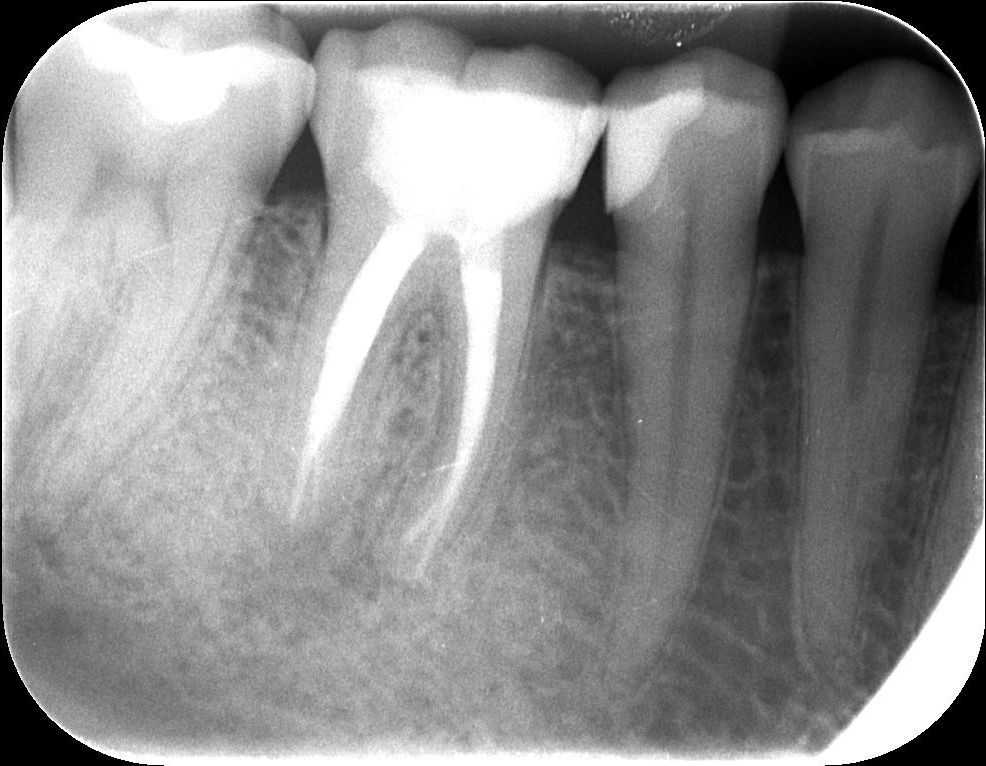

4. röntgenfelvétel

A teljes, kész gyökértömés, illetve az üvegszálas csap beragasztása után készült a felvétel. A csapos megerősítésre azért volt szükség, mert a fog koronájának jó része hiányzott. Ilyenkor a maradék foganyag védelme érdekében vagy öntött vagy üvegszálas csapot helyezünk a fogba.